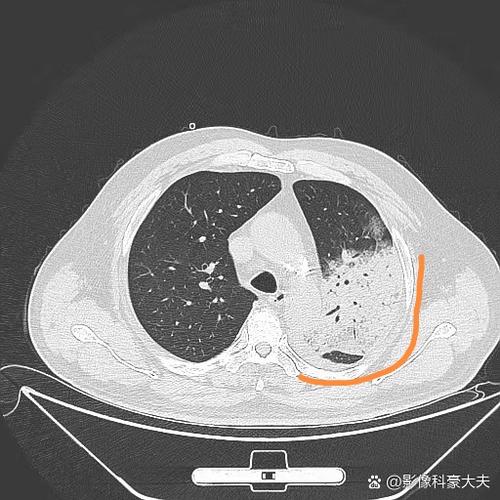

- 通气/血流比例失调: 健康的肺部需要空气(通气)和血液(血流)完美匹配,感染区域有血流但没有足够的空气,而健康区域有空气但血流可能减少,这大大降低了呼吸效率。